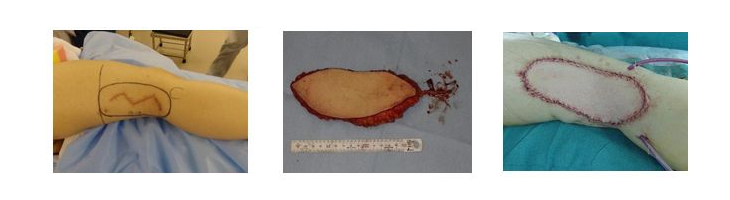

軟部肉腫に対しては手術による腫瘍広範切除術が原則です。術前に造影MRIにて腫瘍の進展範囲を十分に評価した上で切除範囲を設定します。切除により大きな筋肉や皮膚欠損が生じる場合があり、形成外科医のお力をお借りして筋皮弁形成術も併用しています。

膝窩部軟部肉腫切除後、遊離広背筋皮弁による再建術